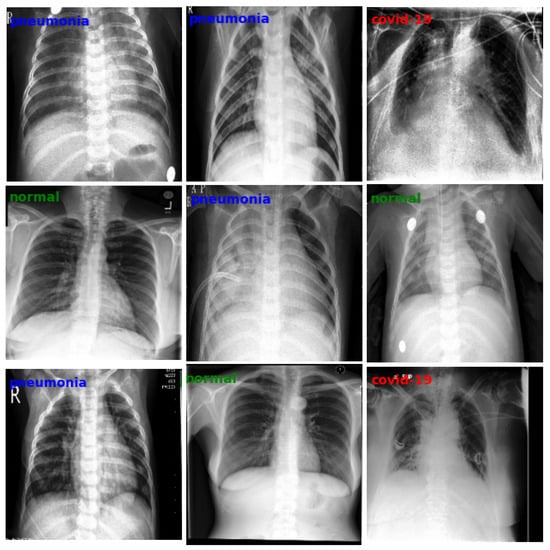

3.1. Dataset